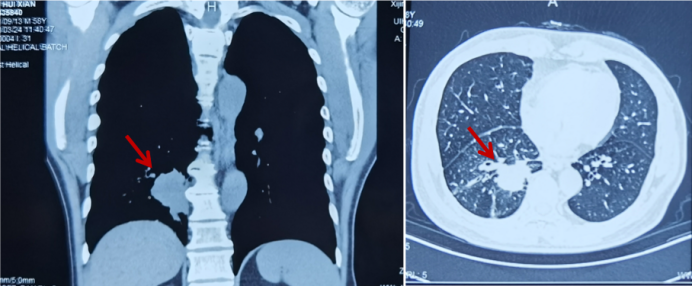

骨骼是肺癌常见的转移部位之一,骨转移癌会导致骨痛、病理性骨折、脊髓压迫、高钙血症等骨相关事件(SRE),其中,骨痛是骨转移癌最常见的临床症状,严重影响患者生活质量。地舒单抗,首个落户中国的核因子κB受体活化因子配体(RANKL)抑制剂,为防治SRE提供新的选择。本次分享地舒单抗治疗以骨痛为主要症状的EGFR突变晚期肺癌骨转移患者案例,希望为SRE的防治带来启迪与思考。 白引苗 空军军医大学第一附属医院肿瘤科 主治医师 中国抗癌协会肿瘤标志物专业委员会 委员 陕西省抗癌协会肿瘤化疗专业委员会 委员 陕西省抗癌协会肿瘤热疗专业委员会 委员 陕西省抗癌协会多原发和不明原发肿瘤专业委员会委员 擅长食管癌、胃癌、结直肠癌、胰腺癌等消化系统、肺癌及妇科常见恶性肿瘤的化疗、靶向治疗及免疫治疗等内科治疗。参译著作1部,参编著作1部,发表核心期刊论文多篇。 一般资料:患者男性,60岁 主诉:右侧肩部疼痛 现病史:2019年8月因右侧肩部疼痛于外院就诊,疼痛NRS评分3-4分,口服依托考昔症状可缓解 个人史:否认吸烟、饮酒嗜好 家族史:1兄因“胃癌”病故 辅助检查: 外院右肱骨MRI:右侧肱骨骨转移可能,合并肱骨中段骨质破坏。 外院胸部CT(图1):右肺下叶周围型肺癌,可疑肺门、纵隔淋巴结转移,T3/4/8椎体骨转移。 图1 胸部CT(箭头指示右肺下叶病变) PET/CT(18F-FDG)(图2-3):右肺下叶基底段软组织病变(3.7 cm×4.6 cm×4.7 cm,SUV max 6.9,平均值6),浅分叶、边缘见毛刺;右侧锁骨上下区、隆突区稍大淋巴结(长径0.6 cm-1.4 cm,SUV max 2.5-4.6,平均值2.2-3.2),考虑转移;脊柱多个椎体及附件、双侧多个肋骨、骨盆多处、双侧股骨上段多发骨质破坏(SUV max 2.0-5.7,平均值1.7-3.9),考虑转移。 图2 PET/CT提示右肺下叶基底段病变及右锁骨上下区、隆突区稍大淋巴结 图3 PET/CT提示多发骨质破坏 患者接受CT引导下经皮右肺病变穿刺活检,病理(图4):光镜见异型细胞呈条索状、腺管样排列,细胞核大、深染,异型性明显;免疫组化:AE1/AE3(+),CK5/6(-),CK7(+),CK8/18(+),P40(-),P63(-), Napsin A(+),ALK(D5F3 Ventana IHC)(-),TTF-1(+),Ki67 30%,支持腺癌。 肿瘤标志物:CYFRA21-1 5.8 ng/ml(参考值:0-3.3 ng/ml),CEA、SCC、NSE正常。 基因检测:EGFR基因19del突变。KRAS、NRAS、PIK3CA、BRAF、HER-2基因未检测到突变;ALK、ROS1、RET基因未检测到融合。 诊断:肺恶性肿瘤(右侧,腺癌,cT2N3M1,IV期,EGFR 19del);骨继发恶性肿瘤(多发);淋巴结继发恶性肿瘤(多发)。 双管齐下、并驾齐驱——抗癌治疗与唑来膦酸齐头并进 2019年9月患者接受奥希替尼80 mg/日一线治疗,同时接受唑来膦酸4 mg/月改善SRE。1个月后复查CT示右肺病变缩小40%(4.7 cm至2.8 cm);肿瘤标志物CYFRA21-1由5.8 ng/ml降至3.67 ng/ml;右肩部疼痛消失(停用止痛药)。 2020年3月复查胸部CT(图5)提示:肺部病变进展(增大39.3%,2.8 cm至3.9 cm);肿瘤标志物CYFRA21-1缓慢升高至7.05 ng/ml。考虑局部进展,在奥希替尼基础上联合培美曲塞+卡铂治疗4个周期,后给予奥希替尼联合培美曲塞维持治疗14个周期。 图5 胸部CT(2020年3月,箭头指示右肺病变) 最佳疗效:右肺病变缩小51.3%(至1.9 cm)(图6);肿瘤标志物CYFRA21-1由7.05 ng/ml降至1.4 ng/ml。 图6 二线治疗前(左图)后(右图)胸部CT比较(箭头指示右肺病变) 2021年4月患者感背部钝痛,NRS评分5-6分,口服氨酚羟考酮330 mg/8 h,症状可缓解。骨扫描(ECT)与单光子发射计算机断层扫描(SPECT)/CT提示骨转移加重。停用唑来膦酸,使用地舒单抗120 mg/月,疼痛有缓解。 2021年9月复查胸部CT示右肺下叶病变进展(1.9 cm至3.4 cm)。肿瘤标志物CYFRA21-1由10.73 ng/ml升至13 ng/ml。患者感背部疼痛加重,NRS 评分5-6分。行CT引导下右肺病变再次穿刺活检,病理提示肺腺癌,PD-L1(SP263)(TPS=80%),Ki67 85%。基因检测:EGFR 19del,KRAS、NRAS、PIK3CA、BRAF、HER-2基因及MET exon14无突变;ALK、ROS1、RET基因无融合。 遂调整为白蛋白结合型紫杉醇化疗2周期,奥希替尼和地舒单抗方案同前,患者背部疼痛消失。 2021年11月复查PET/CT:原右肺下叶基底段团块状软组织病变较初诊缩小(1.8 cm×1.6 cm×3.8 cm);原右侧锁骨区多发淋巴结消失;原隆突区稍大淋巴结缩小(0.5 cm);原脊柱多个椎体及附件、双侧多个肋骨、骨盆多处、双侧股骨上段多发骨质破坏,病变密度增高,考虑治疗有效,部分仍有代谢活跃;右侧颞叶片状低密度影。查头颅MRI(图7):左侧额叶大脑镰旁(0.7 cm×0.7 cm×1 cm)、右侧颞叶脑皮质表面(1.2 cm×1.3 cm×0.8 cm)异常强化灶,考虑转移。 图7 头颅MRI(箭头指示颅内病变) 经MDT讨论,建议脑部病变随诊观察。鉴于出现脑转移癌,调整为伏美替尼80 mg/日口服、白蛋白结合型紫杉醇静脉化疗;继续予地舒单抗。 患者治疗期间碱性磷酸酶(ALP)水平变化如图8所示。 图8 血清碱性磷酸酶变化情况 患者于2019年8月因右侧肩部疼痛就诊,确诊右肺腺癌Ⅳ期伴多发骨转移及淋巴结转移,EGFR 19del突变。一线治疗:奥希替尼(80 mg/日)+骨改良药物唑来膦酸(4 mg/月),最佳疗效:右肺肿瘤PR(缩小40%)、疼痛症状缓解,一线治疗PFS时间7个月。2020年3月,肺部病灶进展,予奥希替尼+培美曲塞联合卡铂4周期,后培美曲塞维持治疗14周期,继续予唑来膦酸治疗;2021年4月背部钝痛加重,骨扫描提示骨病变进展,遂停用唑来膦酸,予地舒单抗120 mg/月治疗至2021年9月,二线PFS 18个月。后因肺部病灶进展,三线治疗给予奥希替尼+白蛋白结合型紫杉醇及地舒单抗,患者背部疼痛症状消失。2021年11月头颅MRI示颅内转移,调整为予伏美替尼(80 mg/日)联合白蛋白结合型紫杉醇及地舒单抗治疗。 张红梅 西京医院肿瘤科主任 肿瘤学博士,硕士研究生导师 中国抗癌协会CMUP 副主委 中国临床肿瘤学会免疫专家委员会 常委 陕西省医学会肿瘤内科分会 副主委 主要从事肺癌等恶性肿瘤的内科治疗 我国肺癌发病率和死亡率均位于恶性肿瘤首位,20%-30%的晚期肺癌会发生骨转移[1],45%的肺癌骨转移患者会出现相关临床症状[2]。肺癌骨转移是患者生活质量降低、生存期缩短的独立危险因素,SRE如骨痛、病理性骨折、脊髓压迫等,不仅给患者带来生理上的痛苦与不便,也引发患者心理打击。因此,对于晚期肺癌骨转移患者,在控制原发疾病同时,亟需积极防治SRE,以达到提高患者生活质量、缓解生理心理痛苦、延长生存期的目的[3]。 本例肺癌同时性骨转移案例,以骨痛为首发症状,在奥希替尼治疗肺癌同时,首先予以唑来膦酸防治SRE,治疗初期患者症状一度改善。但随着疾病进展,唑来膦酸应用近20月后患者再次骨痛加重,影像学提示骨损害加重,对于这种骨病变进展、骨痛加重的临床问题,如何制定进一步治疗方案? 地舒单抗是IgG2型单克隆抗体,通过与RANKL结合,阻止其激活破骨细胞、破骨细胞前体和破骨细胞样巨细胞表面的核因子-κB受体活化因子(RANK),从而达到抑制肿瘤生长、减少骨破坏的目的。早在2010年,地舒单抗获得美国食品药品监督管理局(FDA)批准用于治疗实体瘤骨转移,目前已积累了丰富的证据临床研究和真实世界数据,显示其有效性和安全性。 地舒单抗与唑来膦酸治疗实体瘤骨转移和多发性骨髓瘤的Ⅲ期临床研究显示,地舒单抗可延缓首次出现SRE的时间(21.4个月 VS. 15.4个月)[4]。其中非小细胞肺癌患者,地舒单抗组较唑来膦酸组中位生存期(OS)延长1.5个月(9.5个月 VS. 8.0个月)[5]。安全性方面,地舒单抗也具有一定的优越性:与唑来膦酸组比较,地舒单抗组贫血、厌食症、肾脏不良事件、新发原发性恶性肿瘤的发生率较低[6]。地舒单抗通过网状内皮系统清除,不增加肾脏负担,对于肾功能不全的患者可作为首选。此外,作为皮下注射制剂,28天用药一次,无需住院完成,无疑为口服靶向药的肺癌骨转移患者带来极大的便利。 本例患者经唑来膦酸治疗后再次出现SRE,改用地舒单抗治疗至今,患者骨痛症状缓解,随访血清ALP水平逐渐下降,且耐受性良好。对这位长期与肺癌抗争的晚期患者,地舒单抗减轻了身体的疼痛,带来心灵的慰藉,实现临床获益。 2020年11月20日,地舒单抗在中国获得国家药品监督管理局(NMPA)批准,用于预防实体瘤骨转移及多发性骨髓瘤引起的SRE,随着药物可及性的进一步提高,期待地舒单抗可造福更多饱受骨转移折磨的中国肿瘤患者。 参考文献 1、Her nandez R K , Wade S W, Ly man GH, et al. I ncidence of bone metastases in patients with solid tumors: analysis of oncology electronic medical records in the United States. BMC Cancer, 2018, 18(1): 44. 2、Tsuya A, Kurata T, Tamura K, et al. Skeletal metastases in non-small cell lung cancer: a retrospective study. Lung Cancer, 2007, 57(2): 229-232. 3、北京医学奖励基金会肺癌青年专家委员会,中国胸外科肺癌联盟. 肺癌骨转移诊疗专家共识(2019版)[J]. 中国肺癌杂志, 2019, 22(4): 187-207. 4、Henry D, Vadhan-Raj S, Hirsh V, et al. Delaying skeletal-related events in a randomized phase 3 study of Denosumab versus zoledronic acid in patients with advanced cancer: an analysis of data from patients with solid tumors. Support Care Cancer. 2014 Mar; 22(3): 679-687. 5、Scagliotti GV, Hirsh V, Siena S, et al. Overall survival improvement in patients with lung cancer and bone metastases treated with Denosumab versus zoledronic acid: subgroup analysis from a randomized phase 3 study. J Thorac Oncol. 2012 Dec; 7(12): 1823-1829. 6、Fengxia Chen, Feifei Pu. Safety of Denosumab Versus Zoledronic Acid in Patients with Bone Metastases: A Meta-Analysis of Randomized Controlled Trials. Oncol Res Treat. 2016;39(7-8):453-459.基本情况